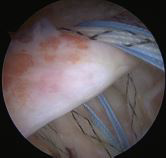

Bei lange andauernden Sehnenrissen können sich diese vom Oberarmkopf zurückziehen. Die Grösse des Sehnenrisses nimmt zu, und die Muskulatur der Rotatorenmanschette baut ab und verfettet. Dies kann so weit führen, dass die Sehnen nicht mehr am Oberarmkopf angenäht werden können. Solche irreparablen Rotatorenmanschettenrisse können zu Schulterschmerzen und einer Schwäche des betroffenen Armes führen. Teilweise sind die Patienten nicht mehr fähig, den Arm zu heben. Infolge der fehlenden Rotatorenmanschetten-Sehnen wird der Oberarmkopf nicht mehr im Gelenk geführt und gehalten und rutscht beim Zug der anderen Schultermuskeln aus der Gelenkspfanne nach oben (Abb. 3). Solche chronischen und stark behindernden Zustände können trotzdem noch zuverlässig behandelt werden: mit einem umgekehrten Kunstgelenk.